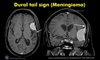

Dural tails are characteristic of _____, which on histology, and also can demonstrate cellular whorls.

Meningiomas